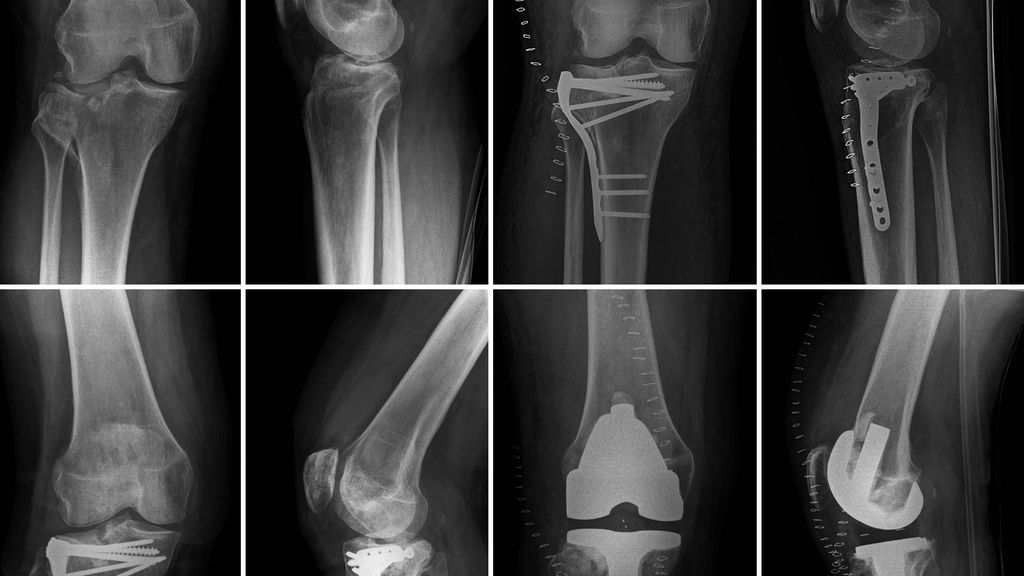

Abb. 1: a, b) 74-jährige Patientin mit Fraktur des lateralen Tibiakondyls und subkapitaler Fibulafraktur, c, d) postoperative Kontrolle nach Implantation einer primären Knieendoprothese 10 Tage posttraumatisch

Als primäre Versorgung innerhalb der Gruppe 1 wurde ein Zeitraum zwischen dem Unfallereignis und der operativen Versorgung mittels Totalendoprothese von maximal zehn Tagen festgelegt. Gruppe 2 wurde primär mit einem osteosynthetischen Verfahren und sekundär mittels Implantation einer Totalendoprothese versorgt; eine Zeitspanne von mindestens 8 Wochen wurde definiert. Drei Patienten konnten nicht erreicht und daher nicht eingeschlossen werden. Das funktionelle Outcome wurde mittels Range of Motion (ROM) evaluiert und statistisch interpretiert. Zudem wurde die Dauer der Hospitalisation aus sozioökonomischer Sicht interpretiert (Abb. 1, 2).

Abb. 2: a, b) 62-jähriger Patient mit Fraktur des lateralen Tibiakondyls, c, d) Zustand nach Osteosynthese, e, f) Einsinken des lateralen Tibiaplateaus sechs Wochen postoperativ, g, h) postoperative Kontrolle nach Implantation einer sekundären Knieendoprothese 6 Monate posttraumatisch